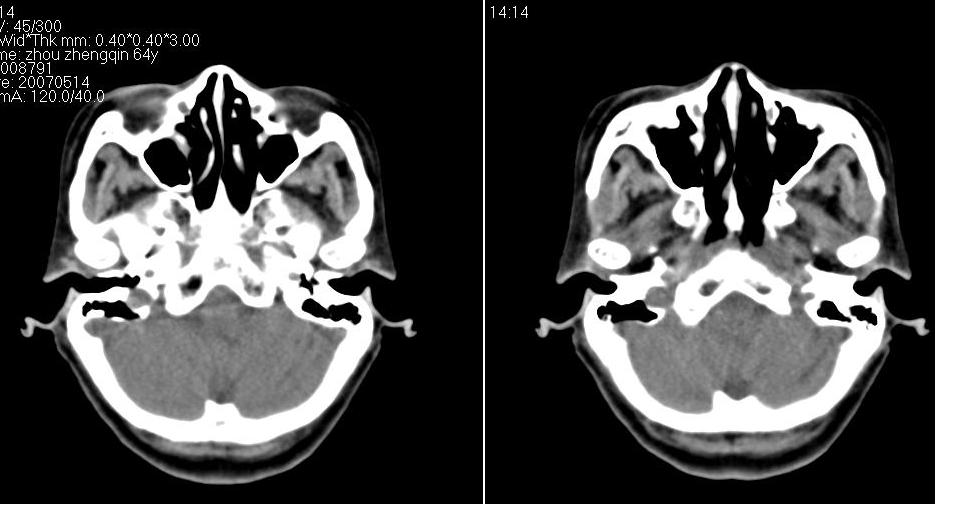

以下是引用zhw974247在2007-5-14 19:34:00的发言:[br]泪腺肿瘤在眶原发性肿瘤中发病率最高,而泪腺混合瘤又是其中最常见者,有良性及恶性二种。良性泪腺混合瘤多见于中年人,病程长,来源于泪腺管或腺泡,也可以起源于副泪腺及先天性胚胎组织残留(泪腺原基)。恶性泪腺混合瘤缺少或无完整的包膜,肿块与眶缘发生粘连,粘连部眶缘有压痛。瘤组织除有良性泪腺混合瘤的结构外,还有癌变的组织构成。瘤组织向眶内浸润,破坏骨质,可发生全身转移,严重者向颅内转移,危及生命。[br]